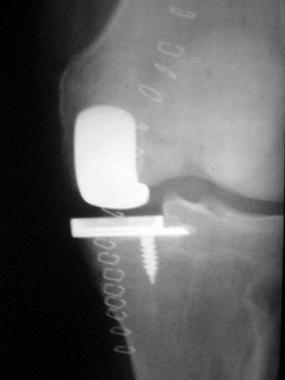

Other considerations for discussion include the sacrifice of the posterior cruciate ligament and the place of unicompartmental knee replacement.[22, 23, 24, 25] In a unicompartmental replacement procedure, it is vitally important to preserve the medial tibial plateau for later revision implantation (see the image below). It is also important to select patients who have only unicompartmental degenerative disease.

Complications of total knee arthroplasty. With unicompartmental prosthesis, it is vitally important to preserve medial tibial plateau for later revision implantation.